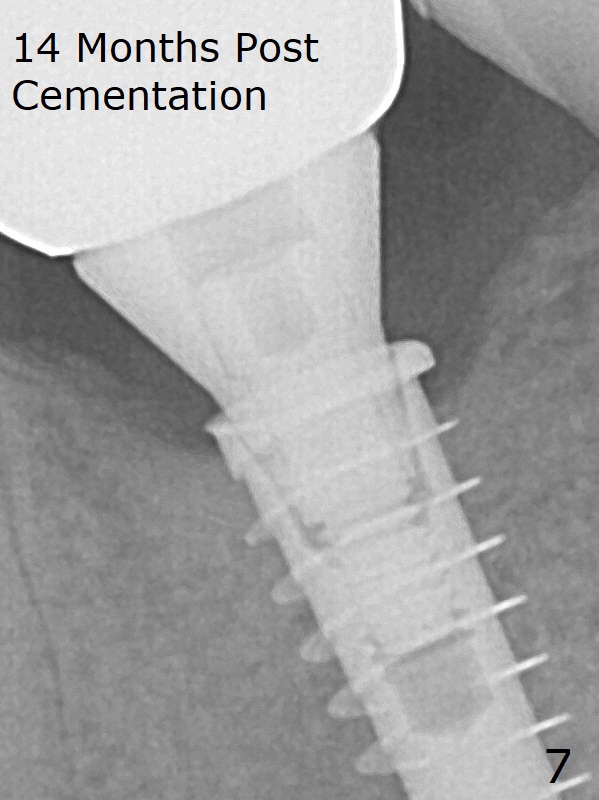

Due to the narrow ridge, a 4.5x11 mm implant is placed (Fig.4); before as well as after placement of a 6x4(3) mm abutment, the mesial socket (*) is filled with Vera graft and autogenous bone as well as collagen plug. Following suturing, periodontal dressing is applied to the wound. There is no apparent bone loss 7 months postop (Fig.5) or 14 months post cementation (Fig.7). In fact the abutment has been incompletely seated, which may be related to #13 failure. The bone density of the crest appears to increase with function.